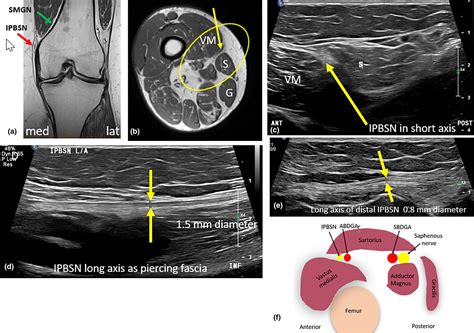

Ultrasound guidance provides a more precise and safer method for performing a Saphenous Nerve Block. The ultrasound probe is placed transversely over the adductor canal, and the saphenous nerve is visualized as a hyperechoic structure surrounded by the femoral artery and vein. The needle is inserted under direct visualization, and the anesthetic is injected around the nerve. This method reduces the risk of complications and improves the accuracy of the block.

• saphenous nerve diagram